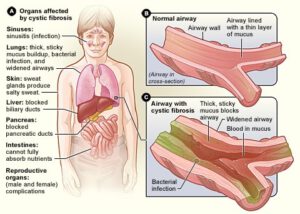

Cystic Fibrosis (CF)

Cheatsheets

2

Mnemonics

0

Images

2

Picmonic

0